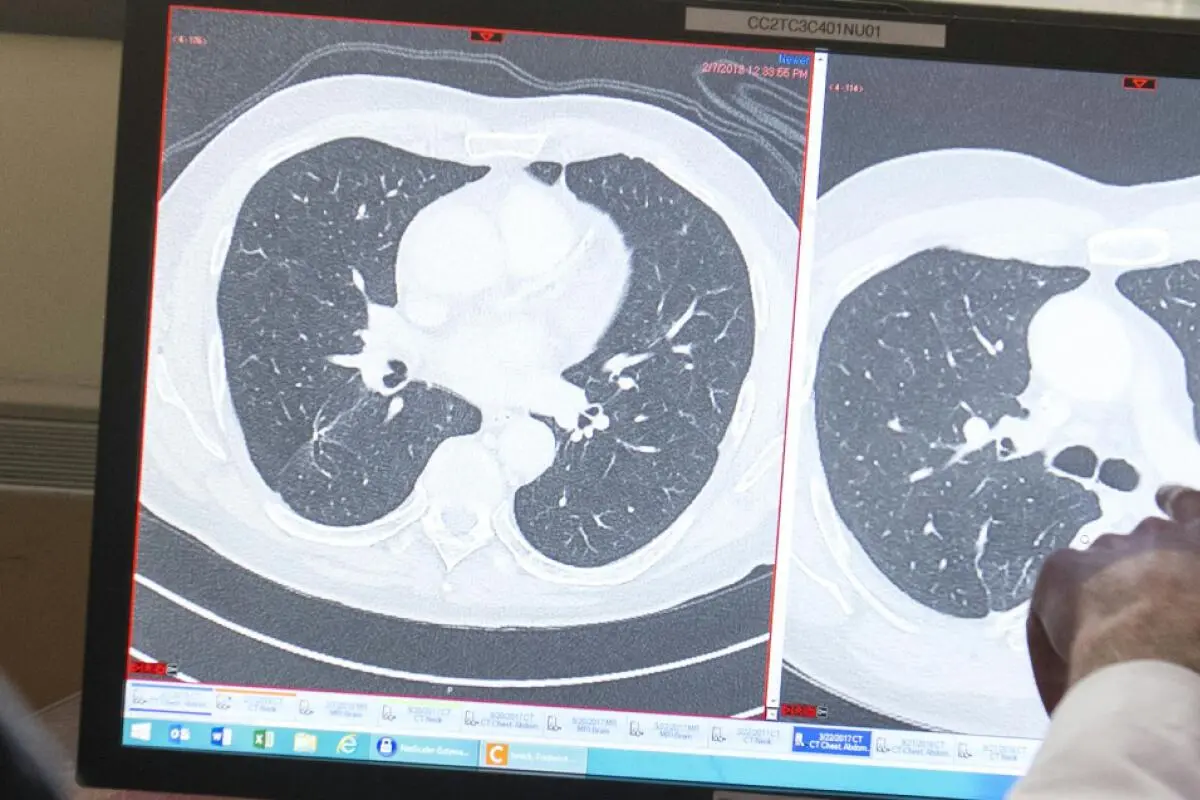

Dr. Christian Hinrichs (R), an investigator at the National Cancer Institute in immunotherapy for HPV+ cancers, shows patient Fred Janick, a survivor of metastatic cancer, the difference between his CT scan showing cancerous tumors (R) and a clean scan after treatment (L), after a day of medical exams showing no recurrence of cancer, at the National Institutes of Health (NIH) in Bethesda, Maryland, February 8, 2018. Experimental trials are ongoing at the National Institutes of Health Clinical Center, a US government-funded research hospital where doctors are trying to partially replace patients' immune systems with T-cells that would specifically attack cancers caused by the human papillomavirus (HPV), a common sexually transmitted infection. A person's T-cells will naturally try to kill off any invader, including cancer, but usually fall short because tumors can mutate, hide, or simply overpower the immune system..Immunotherapies that have seen widespread success, such as chimeric antigen receptor (CAR-T) cell therapies, mainly target blood cancers like lymphoma, myeloma and leukemia, which have a tumor antigen -- like a flag or a signal -- on the surface of the cells so it is easy for immune cells to find and target the harmful cells. But many common cancers lack this clear, surface signal. Hinrichs' approach focuses on HPV tumors because they contain viral antigens that the immune system can easily recognize. (Photo by SAUL LOEB / AFP)